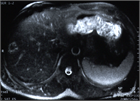

1. エキノコックス症の画像診断において、MRIによる小嚢胞性病変の確認が有用である(推奨度2)